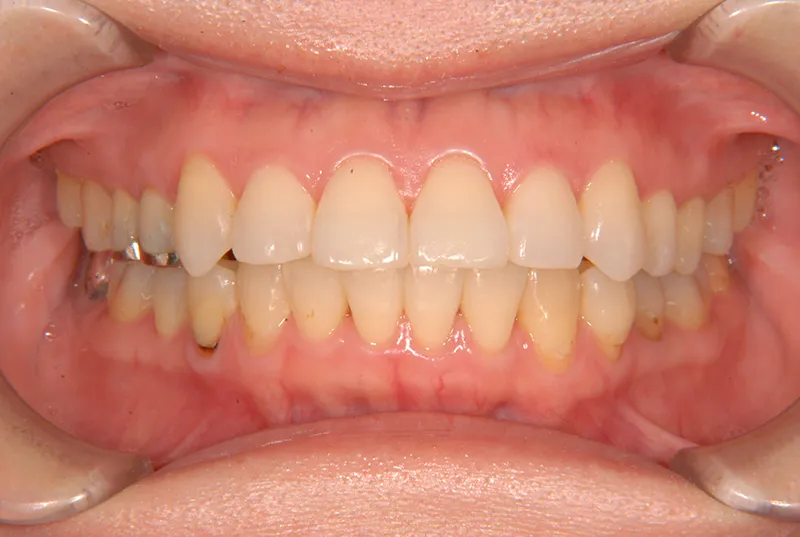

上下のがたがたと噛み合わない事を主訴に来院されました。

歯は抜かずに矯正治療しました。

治療回数35回、2年8ヶ月の治療期間で矯正治療を終了しました。

噛み合わせが安定する事で、大きくなっていた咬筋が正常な大きさになり、顎のラインもシャープになり大変よろこばれていました。

また今回の症例は、歯科矯正用アンカースクリューを用いた治療の本に掲載されました。